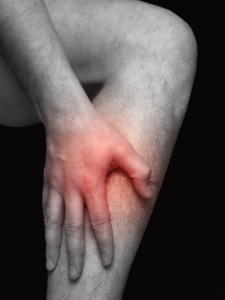

El paciente aquejado de periostitis tibial mostrará dolor y pesadez en la mitad distal de la pierna. Todavía no hay un consenso acerca de la causa de la periostitis, aunque algunos autores achacan como posibles causas la hiperpronación, la distensión de los músculos plantar-flexores, la varificación del antepié o retropié, el aumento rápido de la intensidad del entrenamiento, una falta de aporte de calcio, el uso de calzado deportivo inadecuado o la existencia de una lesión previa mal curada.

En general, el podólogo o el fisioterapeuta podrán determinar la existencia de una periostitis tibial mediante la palpación de la zona afectada, aunque a veces puede ser necesario utilizar un equipo de gammagrafía ósea. Adicionalmente, es importante que el profesional sanitario busque la causa de la lesión, normalmente mediante una exploración biomecánica completa en dinámica.